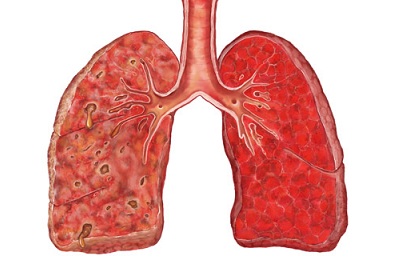

Внутрибольничными пневмониями называются воспалительные заболевания легких с поражением альвеол, которые возникают спустя двое и более суток после госпитализации больного. При этом главную роль в установлении этого диагноза играет исключение инфицирования вне стационара и отсутствие признаков инкубационного периода на момент поступления в лечебное учреждение. Таким образом, нозокомиальная пневмония – воспаление легких, приобретенное в период нахождения больного в пределах лечебного учреждения.

Внутрибольничная пневмония – это легочная инфекция, развившаяся спустя двое и более суток после поступления больного в стационар, при отсутствии признаков заболевания на момент госпитализации. Проявления внутрибольничной пневмонии аналогичны таковым при других формах воспаления легких: лихорадка, кашель с мокротой, тахипноэ, лейкоцитоз, инфильтративные изменения в легких и т. п., однако могут быть слабо выраженными, стертыми. Диагноз основывается на клинических, физикальных, рентгенологических и лабораторных критериях. Лечение внутрибольничной пневмонии включает адекватную антибиотикотерапию, санацию дыхательных путей (лаваж, ингаляции, физиометоды), инфузионную терапию.